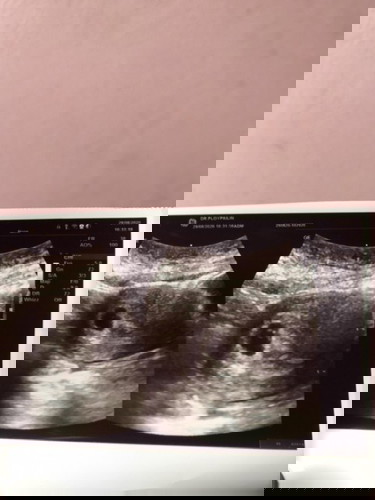

ท้องแล้วจ้า หลังจากที่รอมานาน ปจด.ไม่มา5เดือน แต่ตรวจทุกเดือนไม่ท้อง ควบคู่กับการลดน้ำหนัก ล่าสุดเจ็บหน้าอก ไปตรวจดู กำลังท้องอ่อนๆค่ะ